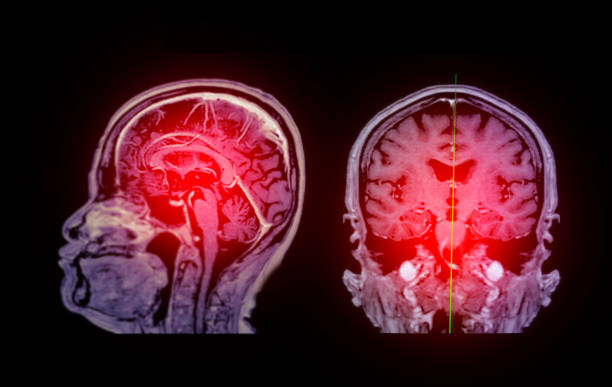

腦缺血缺氧引起的缺血性腦卒中是一種致殘率較高的腦血管疾病。缺血性中風(fēng)是全世界殘疾和死亡的主要原因。據(jù)報(bào)道,缺血性腦卒中30天內(nèi)的死亡率為5%~15%,致殘率可能超過(guò)50%。超過(guò)40%的幸存者再次經(jīng)歷缺血性中風(fēng),死亡率和致殘率更高。

目前,重組組織型纖溶酶原激活劑標(biāo)準(zhǔn)靜脈溶栓療法是臨床上唯一批準(zhǔn)的治療急性腦梗死的藥物療法。然而,這種治療方法也有局限性,主要與其在癥狀出現(xiàn)后4.5小時(shí)的短暫窗口期內(nèi)應(yīng)用有關(guān)。血管內(nèi)介入治療的應(yīng)用也越來(lái)越多,但仍僅適用于大血管閉塞的患者。不適合溶栓治療或血栓切除術(shù)的患者的致殘率甚至更高。康復(fù)治療雖然有助于神經(jīng)功能的恢復(fù),但療效仍然有限。